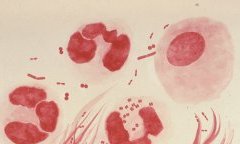

Port-Gentil : Face à une séroprévalence alarmante de 4,1 %, le CTA intensifie la riposte

L’alerte est maximale dans la capitale économique. Avec un taux de séroprévalence de 4,1 %, Port-Gentil dépasse...

VIH à Port-Gentil : 8 061 patients déclarés et non 52 000, le CTA intensifie les dépistages

Face à l’augmentation préoccupante des cas de contamination aux infections sexuellement transmissibles (IST) et au VIH...